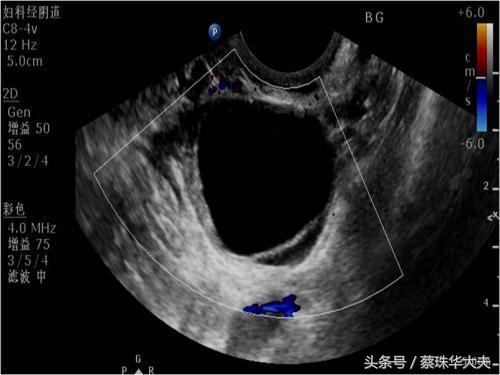

月经正常卵泡发育,所起在排卵前,月经周期28-30天的女性,在月经周期10-14天B超可看见卵泡,影像学看上去就是一个囊肿,这个囊肿大小不等,可以波动在1-3cm,如果当个月有促排卵,那这时候卵巢内卵泡更多,更大。

卵泡囊肿的特点是囊液澄清,囊壁非常光滑。所以很多女性体检是发现卵巢囊肿,一般都建议月经周期第五天或月经干净了马上复查。